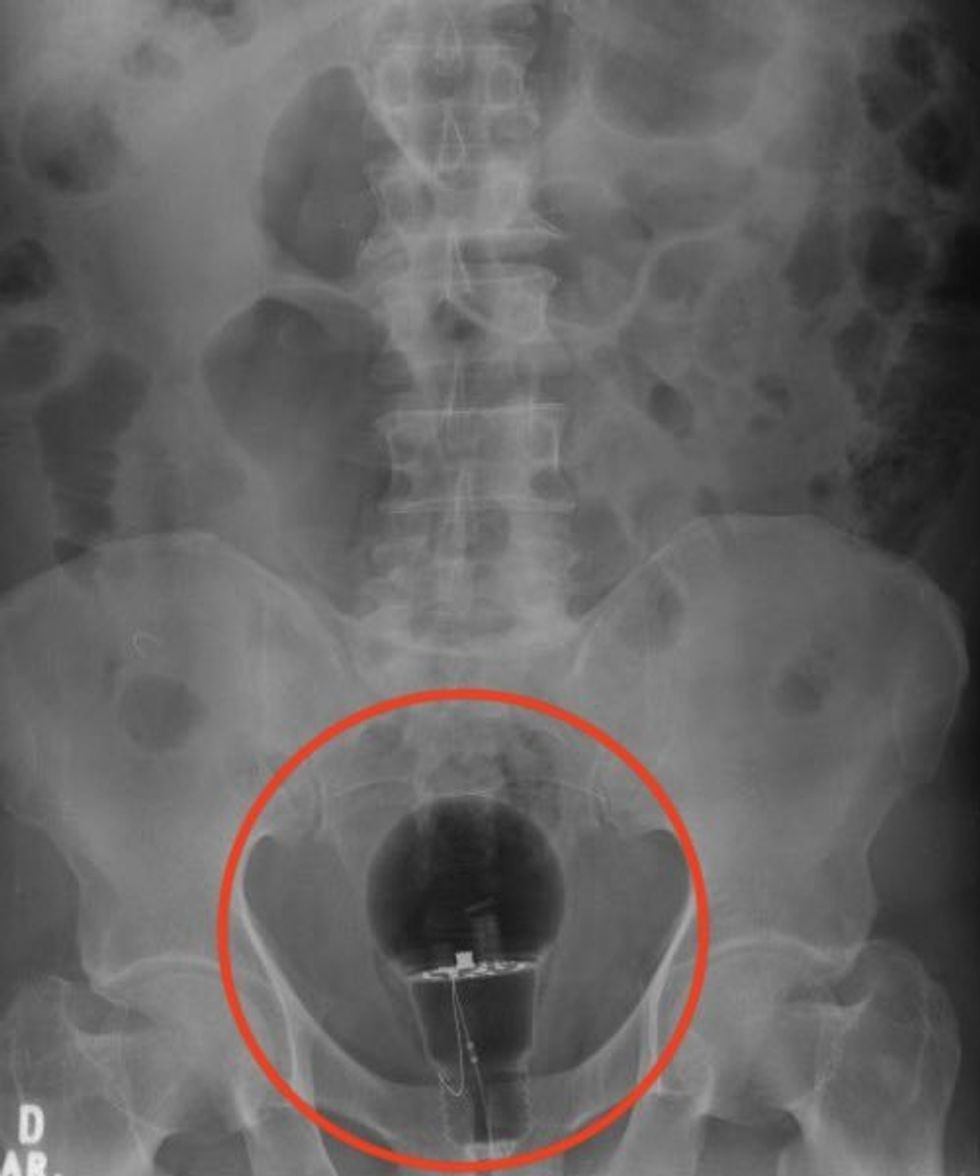

A patient in pain went to the hospital and left doctors stunned when an X-ray showed a lightbulb up his bottom.

Dr Julian Pylori, a gastroenterologist, said the foreign object was not spotted in a normal rectal examination.

But the doctor, who treats digestive disorders, was stunned when the bulb showed up on the X-ray.

Dr Pylori said: “Not palpable on rectal examination.

“Foreign body material, unknown.

“Endoscopic removal?”